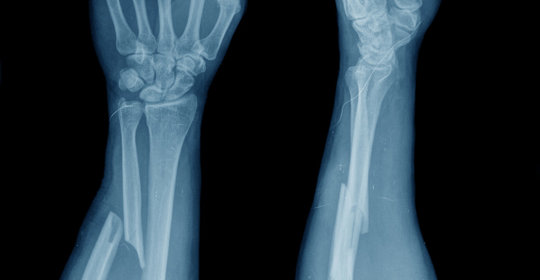

本文介紹了骨質連續性中斷的現象,並強調了及時就醫的重要性。該情況多由外傷導致,如跌倒或車禍,會導致骨骼完整性受損,引起劇烈疼痛、腫脹和功能障礙。診斷常透過X光檢查確認骨折線的存在。治療方案因骨折部位和型別而異,可能涉及固定石膏、手術內固定等方法。